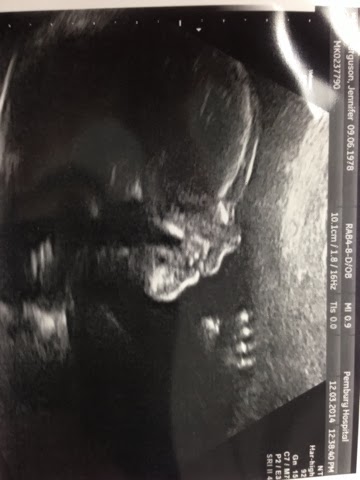

Well, it turns out it’s….

Blogger image